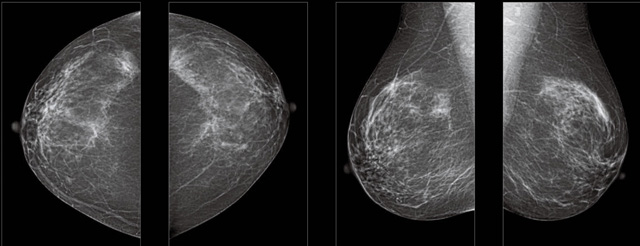

首先不同年齡階段的乳腺篩查頻次種類不一樣。青春期女性第二性征明顯發(fā)育開始,每個月進行自我乳腺檢查。20-30歲的女性就不推薦進行乳腺檢查,因為年輕女性的乳腺組織非常緊急。鉬靶X光線等檢查的射線不能辨別腫塊跟腺體。身體就白吸收了輻射,影響了身體健康。每個月自檢一次就是在洗澡時候,對著鏡子看看乳房外觀正常,皮膚潰爛、腫塊、顏色改變、再摸一下有沒小疙瘩。乳腺高危人群,特別是有乳腺CA遺傳傾向的女性,乳腺導(dǎo)管跟小葉不典型增生,原位癌。30歲前有乳房放療的女性。乳腺癌篩查可以把年齡提前到40歲前。40到70歲的女性可以在適合的機會篩查。

采用影像檢查技術(shù)來發(fā)現(xiàn)疑似特定病檢查跟人群的普查。一到兩年進行一次X光線的乳腺檢查。記過是C或者D型,可以加上B超協(xié)同。還可以一年一次核磁共振MRI檢查。70歲以上的女性認(rèn)為絕經(jīng)的女性是比較安全的。實際上也有乳腺癌的風(fēng)險。65歲以上風(fēng)險也很大。也是需要進行機會性篩查。